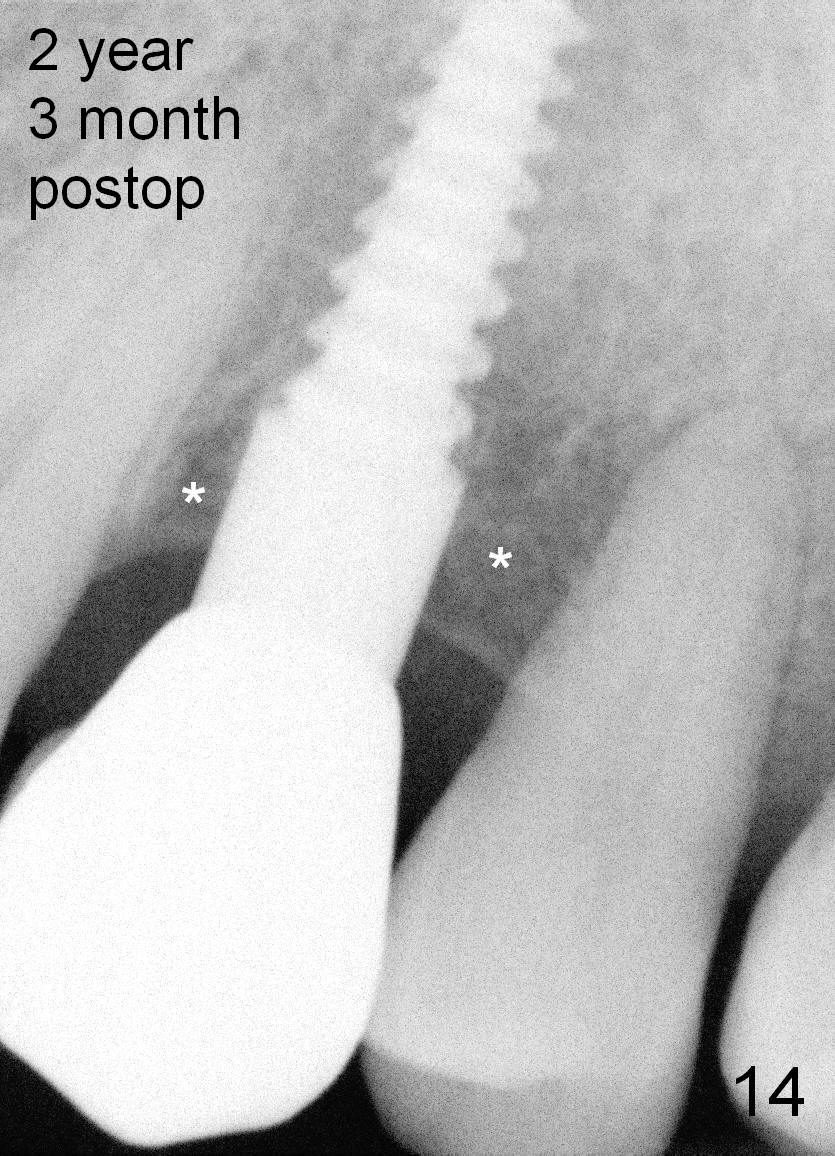

Crestal bone grows 2 months (Fig.11), 3 months (Fig.12), 1 year (Fig.13) and 2 years 3 months (Fig.14) postop. When the periodontally-affected tooth is removed and bone graft is placed around the most coronal thread of the implant, bone will regrow as time passes by.